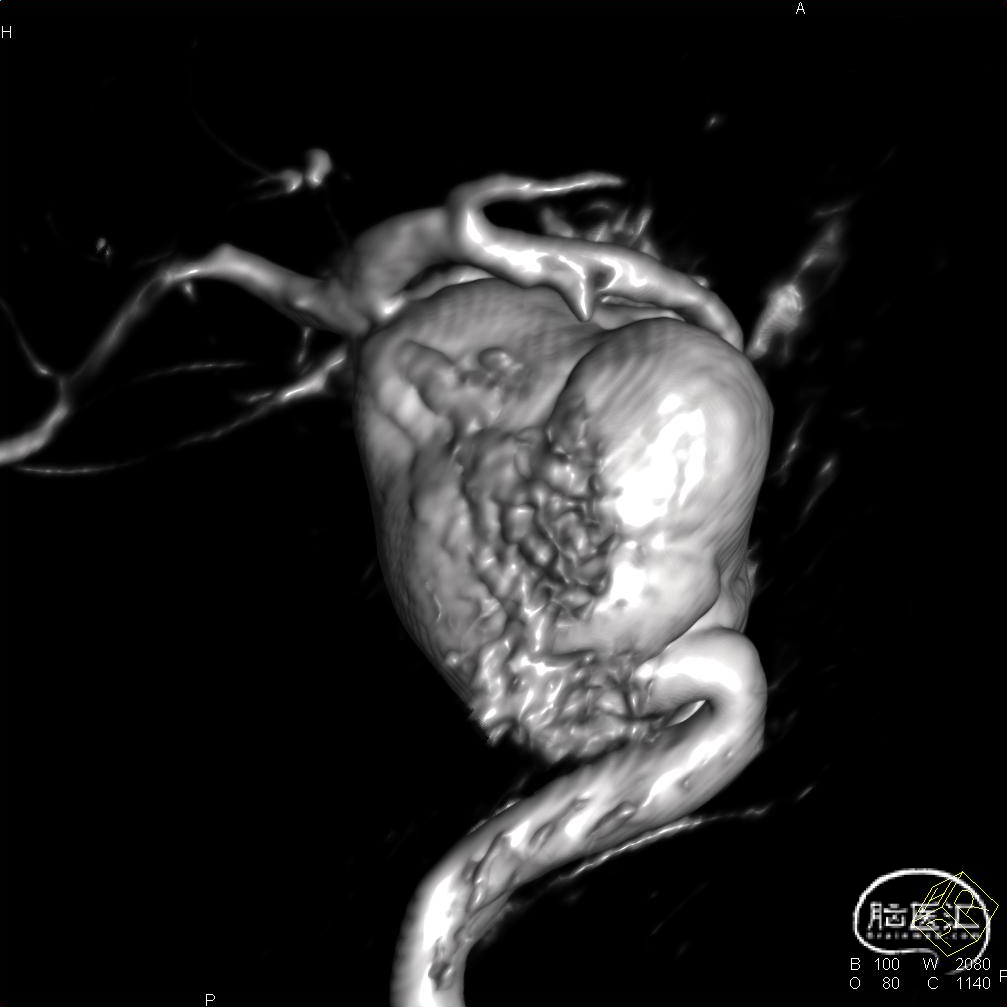

术前CT检查显示,可见左侧侧裂内侧类圆形高密度。

DSA造影显示为左侧颈内动脉海绵窦段巨大动脉瘤。

通过3D工作位测量出左侧海绵窦段动脉瘤尺寸:33mm不规则动脉瘤,载瘤动脉尺寸:近端直径4.55mm,远端直径3.97mm。

造影后发现该患者左侧海绵窦段动脉瘤,动脉瘤不规则,最大径33mm,未破裂,不累及分叉部,动脉路径迂曲。